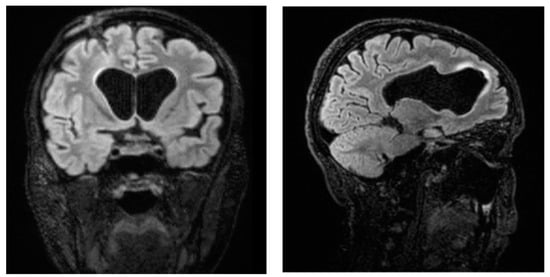

A Difficult Case of Ventriculitis in a 40-Year-Old Woman with Acute Myeloid Leukemia

2. Case Report